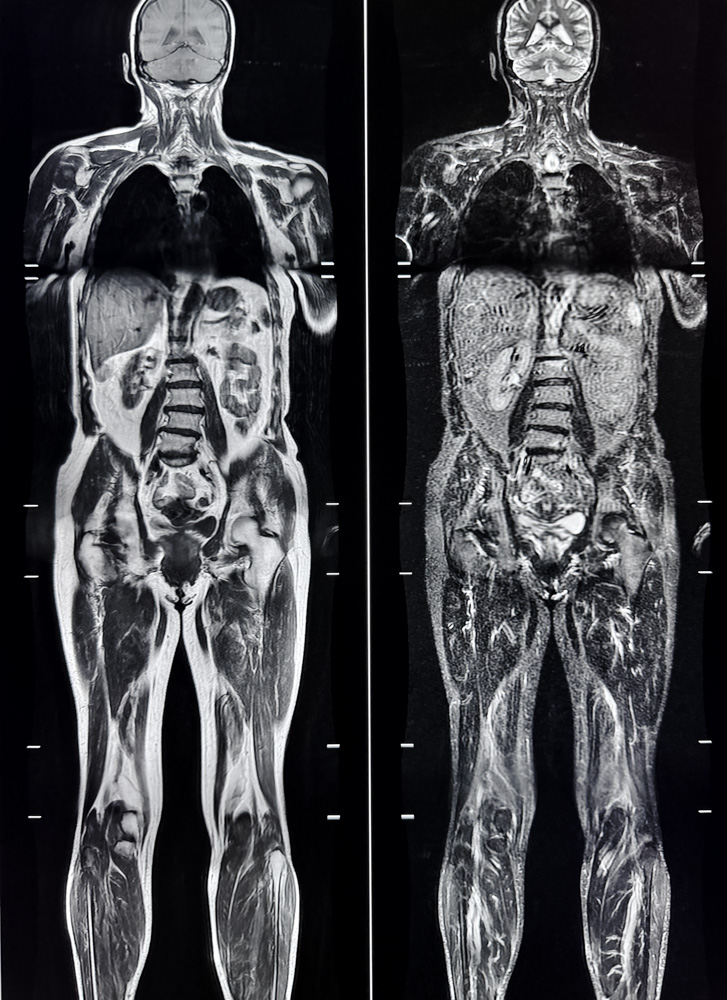

Von Kopf bis Fuß durchschaut.

Dank des enormen technischen Fortschritts der MRT-Forschung, insbesondere der MR-Gradiententechnik und der Herstellung von organspezifischem Kontrastmittel, ist es uns heute möglich, den gesamten menschlichen Körper darzustellen – und dies nicht-invasiv, also ohne Eindringen in den Körper.